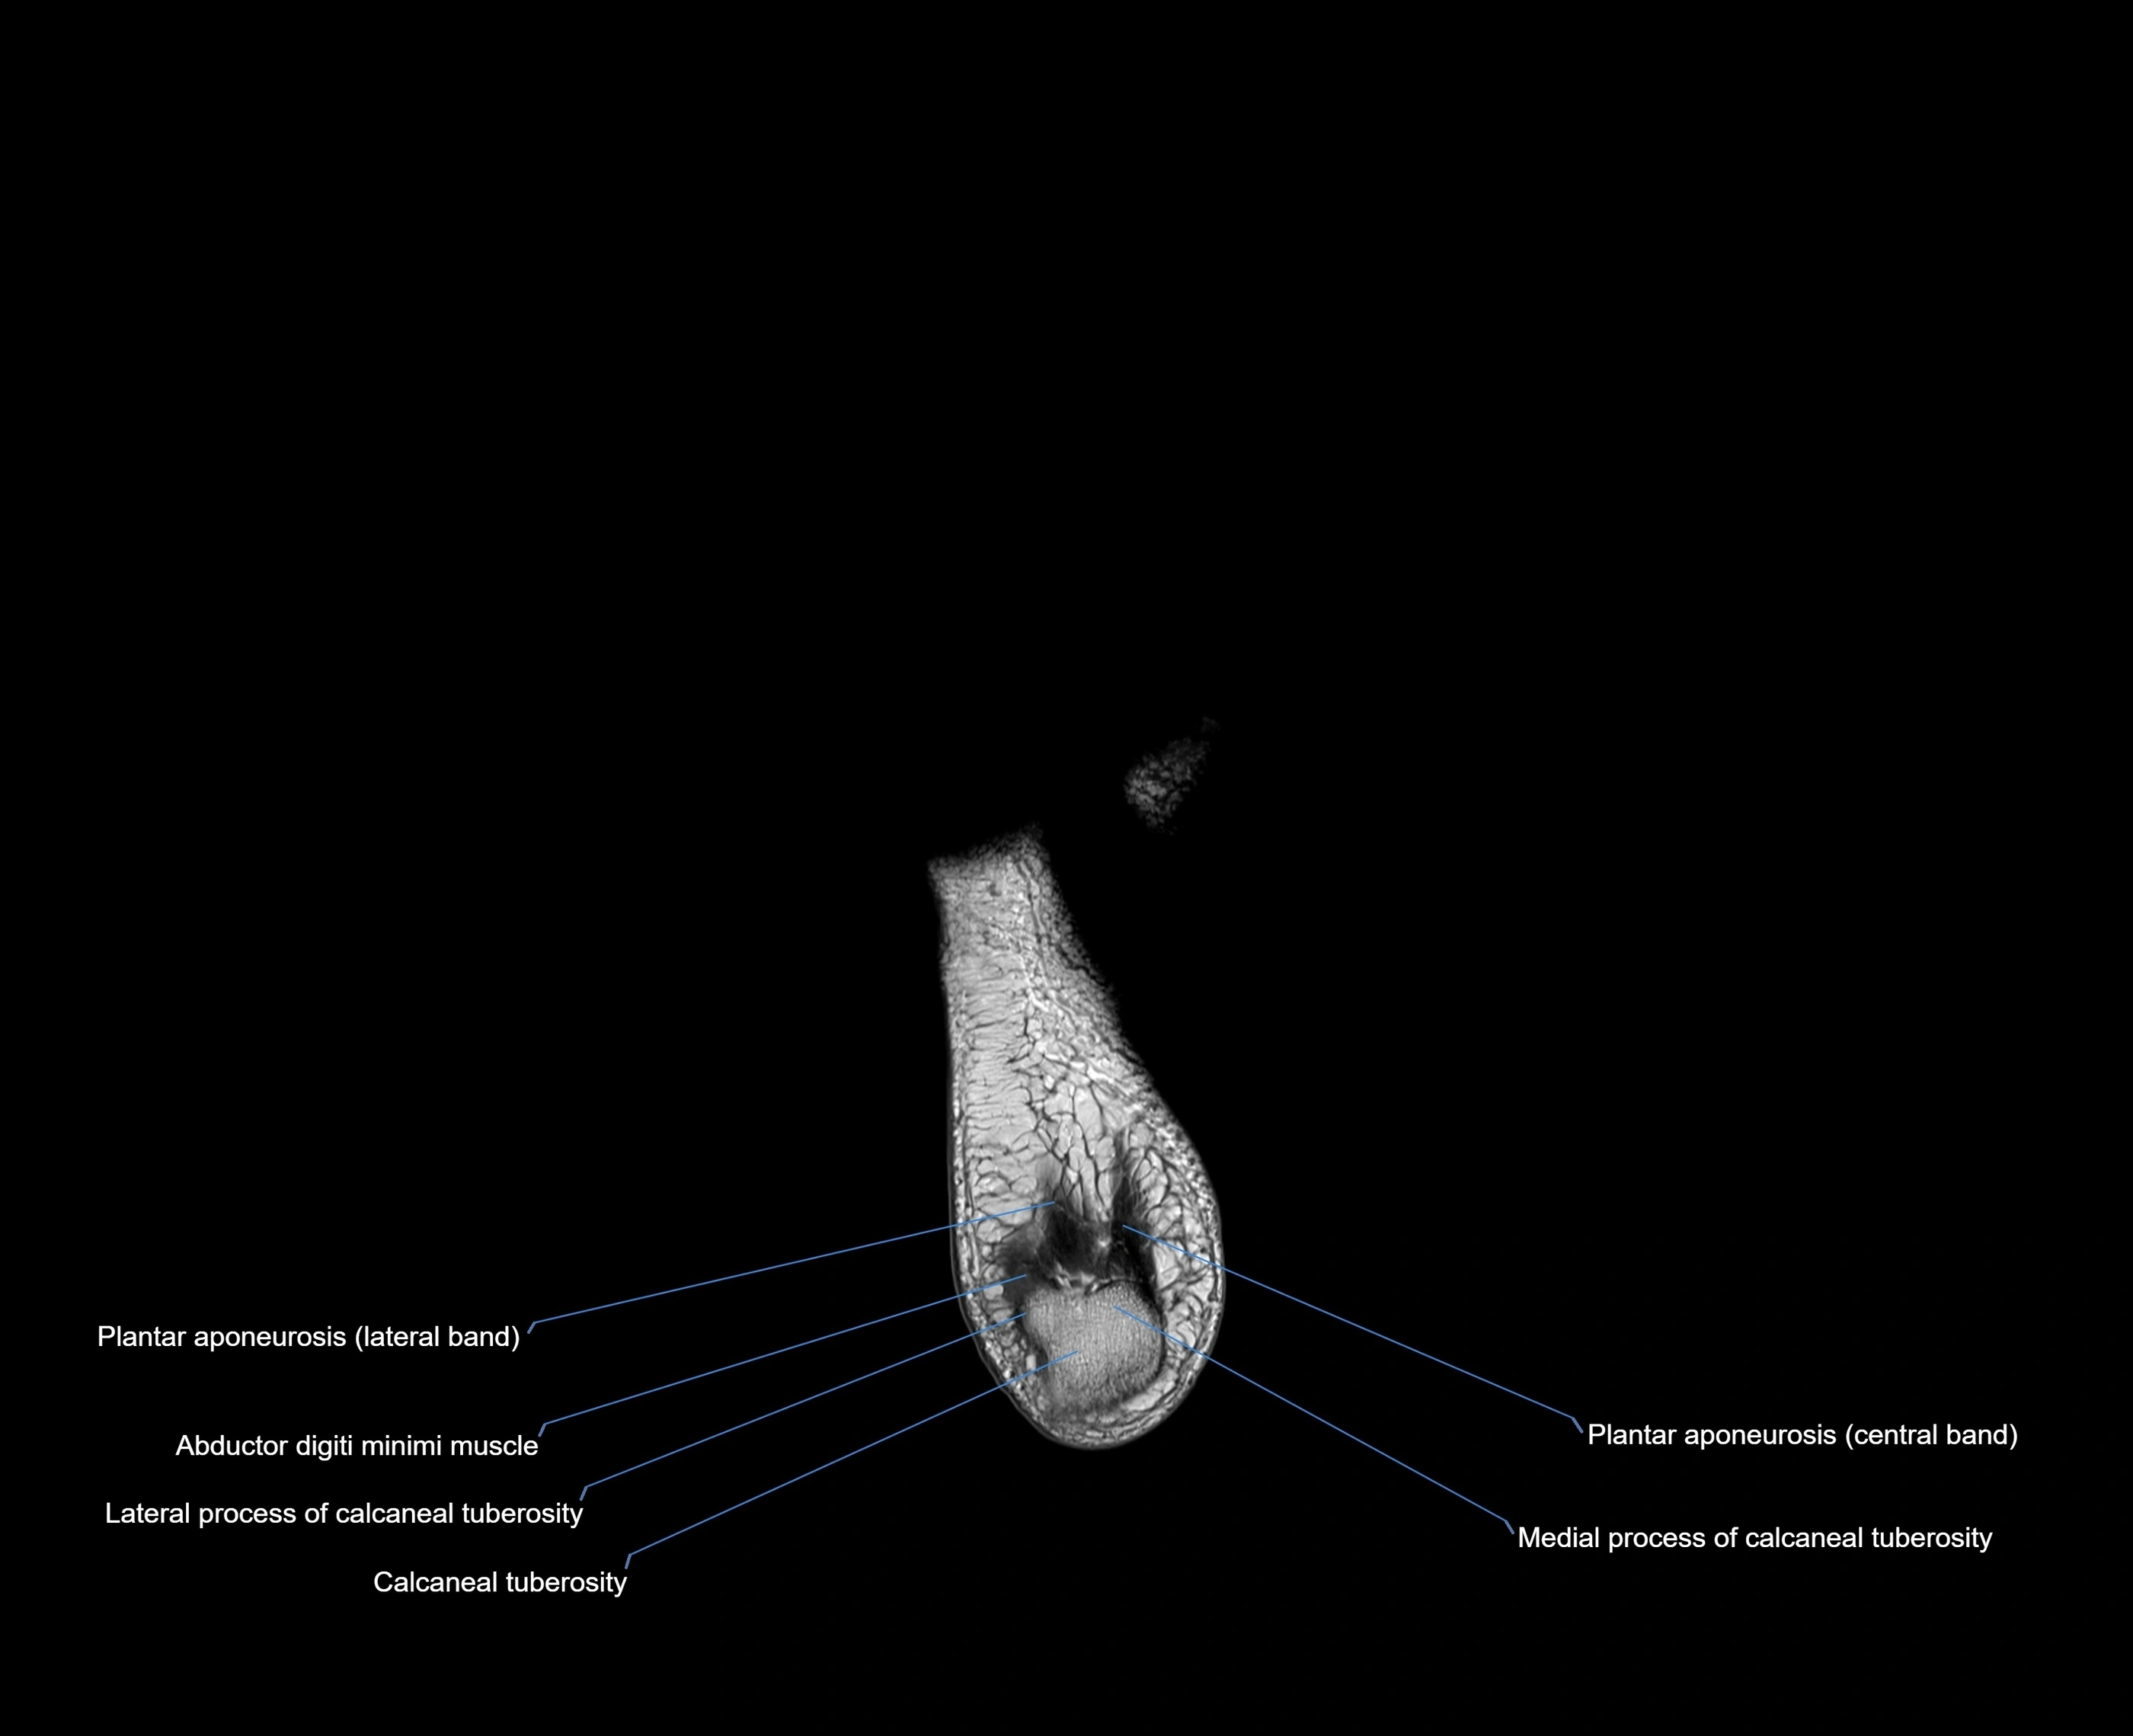

Origin: Medial and lateral processes of the calcaneal tuberosity, plantar aponeurosis, and intermuscular septum

Insertion: Lateral aspect of the base of the proximal phalanx of the 5th toe; sometimes attaches to the tendon of the flexor digiti minimi brevis

Attaches distally into the lateral base of the proximal phalanx of the fifth toe

MRI image